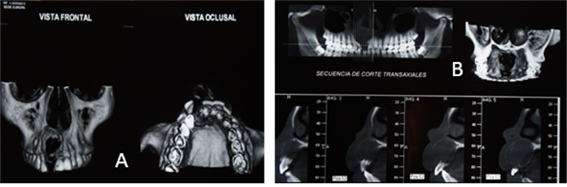

Se procede a evaluar y analizar ortopantomografia inicial, en la cual se evidencia una lesión de aproximadamente 3 cm ya que esto es referencial, evaluación de imágenes de TAC, análisis de informe imageneológico y exámenes de laboratorio, ya con todos estos datos clínicos e imageneológicos, se  procede a la discusión y planificación quirúrgica en la que se decide realizar una enucleación de la lesión y posteriormente realizar estudio histopatológico.

Figura 5. Radiografías y tomografía de haz cónico

Imagen (a) ortopantomografia (b) vista  lateral derecha y vista palatina, tomografía de haz cónico.

Figura 6. Tomografía de haz cónico.

Imagen (a) vista frontal y oclusal (b) cortes transaxiales de tomografía de haz cónico donde se evidencia tamaño y cuanto involucra los órganos dentales con una imagen hipodensa bien definida.